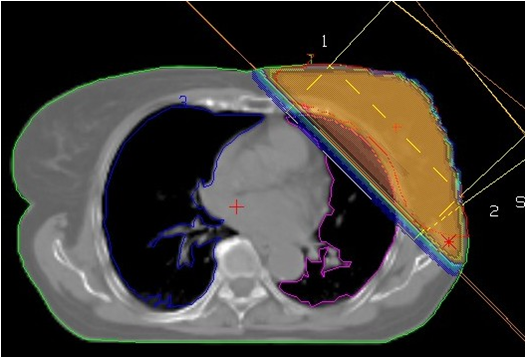

Figure 13, 14, 15: Patient fixation

Figure: 16, 17: Contouring

Figure 18, 19: Treatment planning